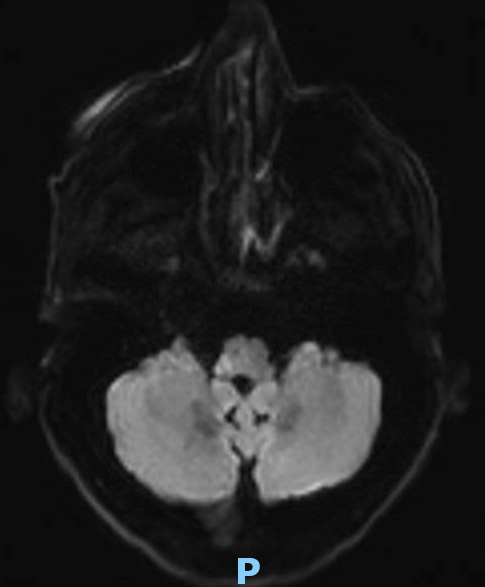

Le type d’hémianopsie est très important car il permet de localiser une atteinte neurologique, en connaissant le trajet des voies optiques.

Cette question supposait d’avoir bien en tête le schéma des voies optiques, et d’avoir des repères sur les principaux territoires vasculaires cérébraux et l’atteinte clinique associée. Il bien mentionné par le CEN que l’hémianopsie latérale homonyme gauche peut se voir dans un AVC sylvien superficiel droit.